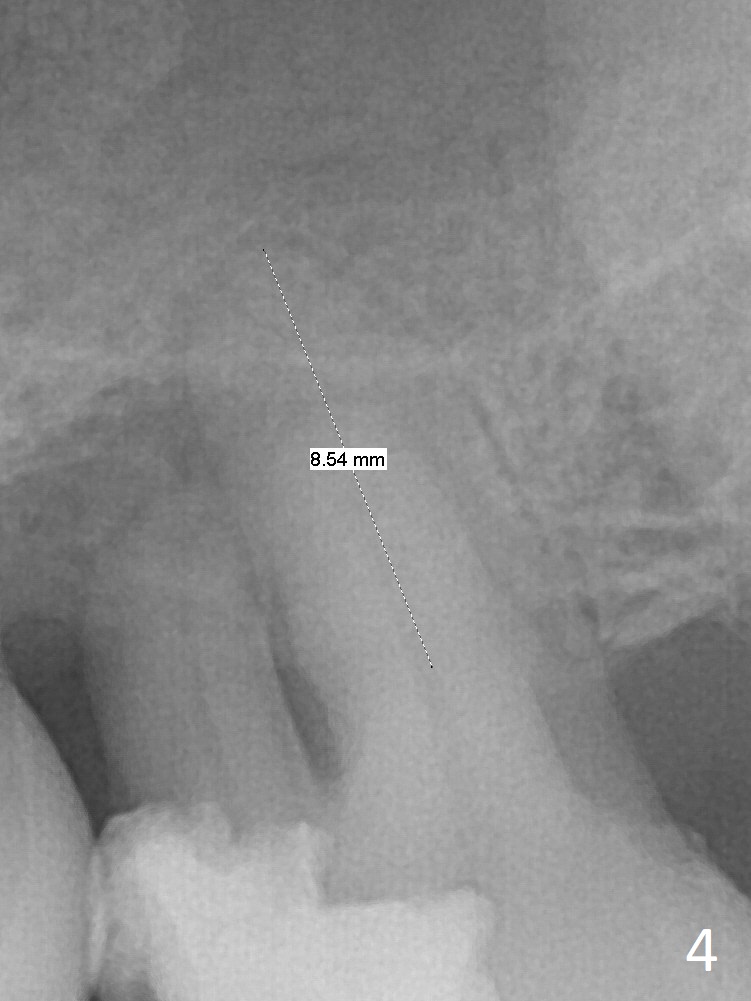

Bone loss seems to be the most severe around the mesiobuccal root (Fig.2 *), from which the osteotomy should stay away (Fig.3). It may be the safest to place an implant in the palatal socket, leaned as buccally as possible so that the coronal end of the implant will be in the center of the extraction socket. Re-measure the palatal socket length from PA and Pan: 8.5 and 10 mm, respectively. The implant length should be around 10 mm. Place bone graft before the final tap and take X-ray.